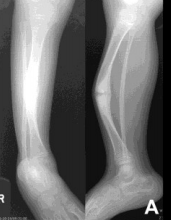

What do the arrows indicate? | Infectious periostitis |

What disease is this? What signs indicate this? | Osteomyelitis. Osteolysis (fragmentation), sequestra (dead/necrotic bone fragments floating in pus), rarefacation (loss of bone density). |

What disease is this? What do A, B & C show? | Osteomyelitis. A = Soft tissue swelling B = Periosteal reaction C = Bony destruction |